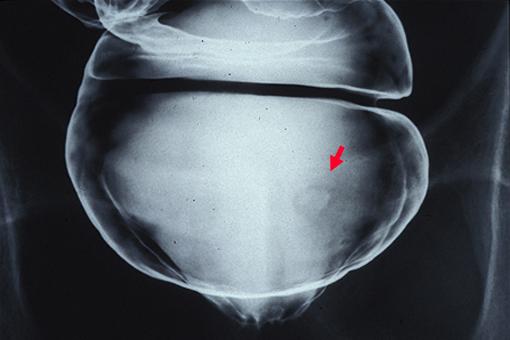

症例提示(所在地,施設名等): 東京都・ 国立がんセンター中央病院

疾患(病理主体)の分類腫瘍様病変/異所性粘膜

部位(臓器別)大腸/直腸

検査方法X-P

病変の最大径(ミリ)10〜14